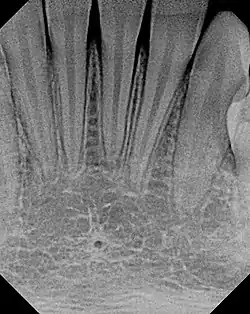

The small lingual foramen (black "hole" in lower portion of picture) as seen on a periapical radiograph of the anterior mandible.